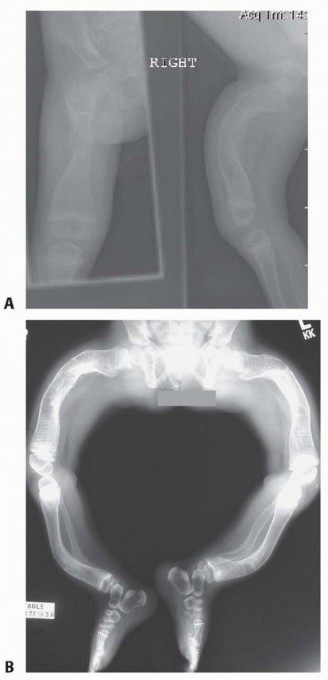

Multiple Percutaneous Osteotomies and Fassier-Duval Telescoping Nailing of Long Bones in Osteogenesis Imperfe…